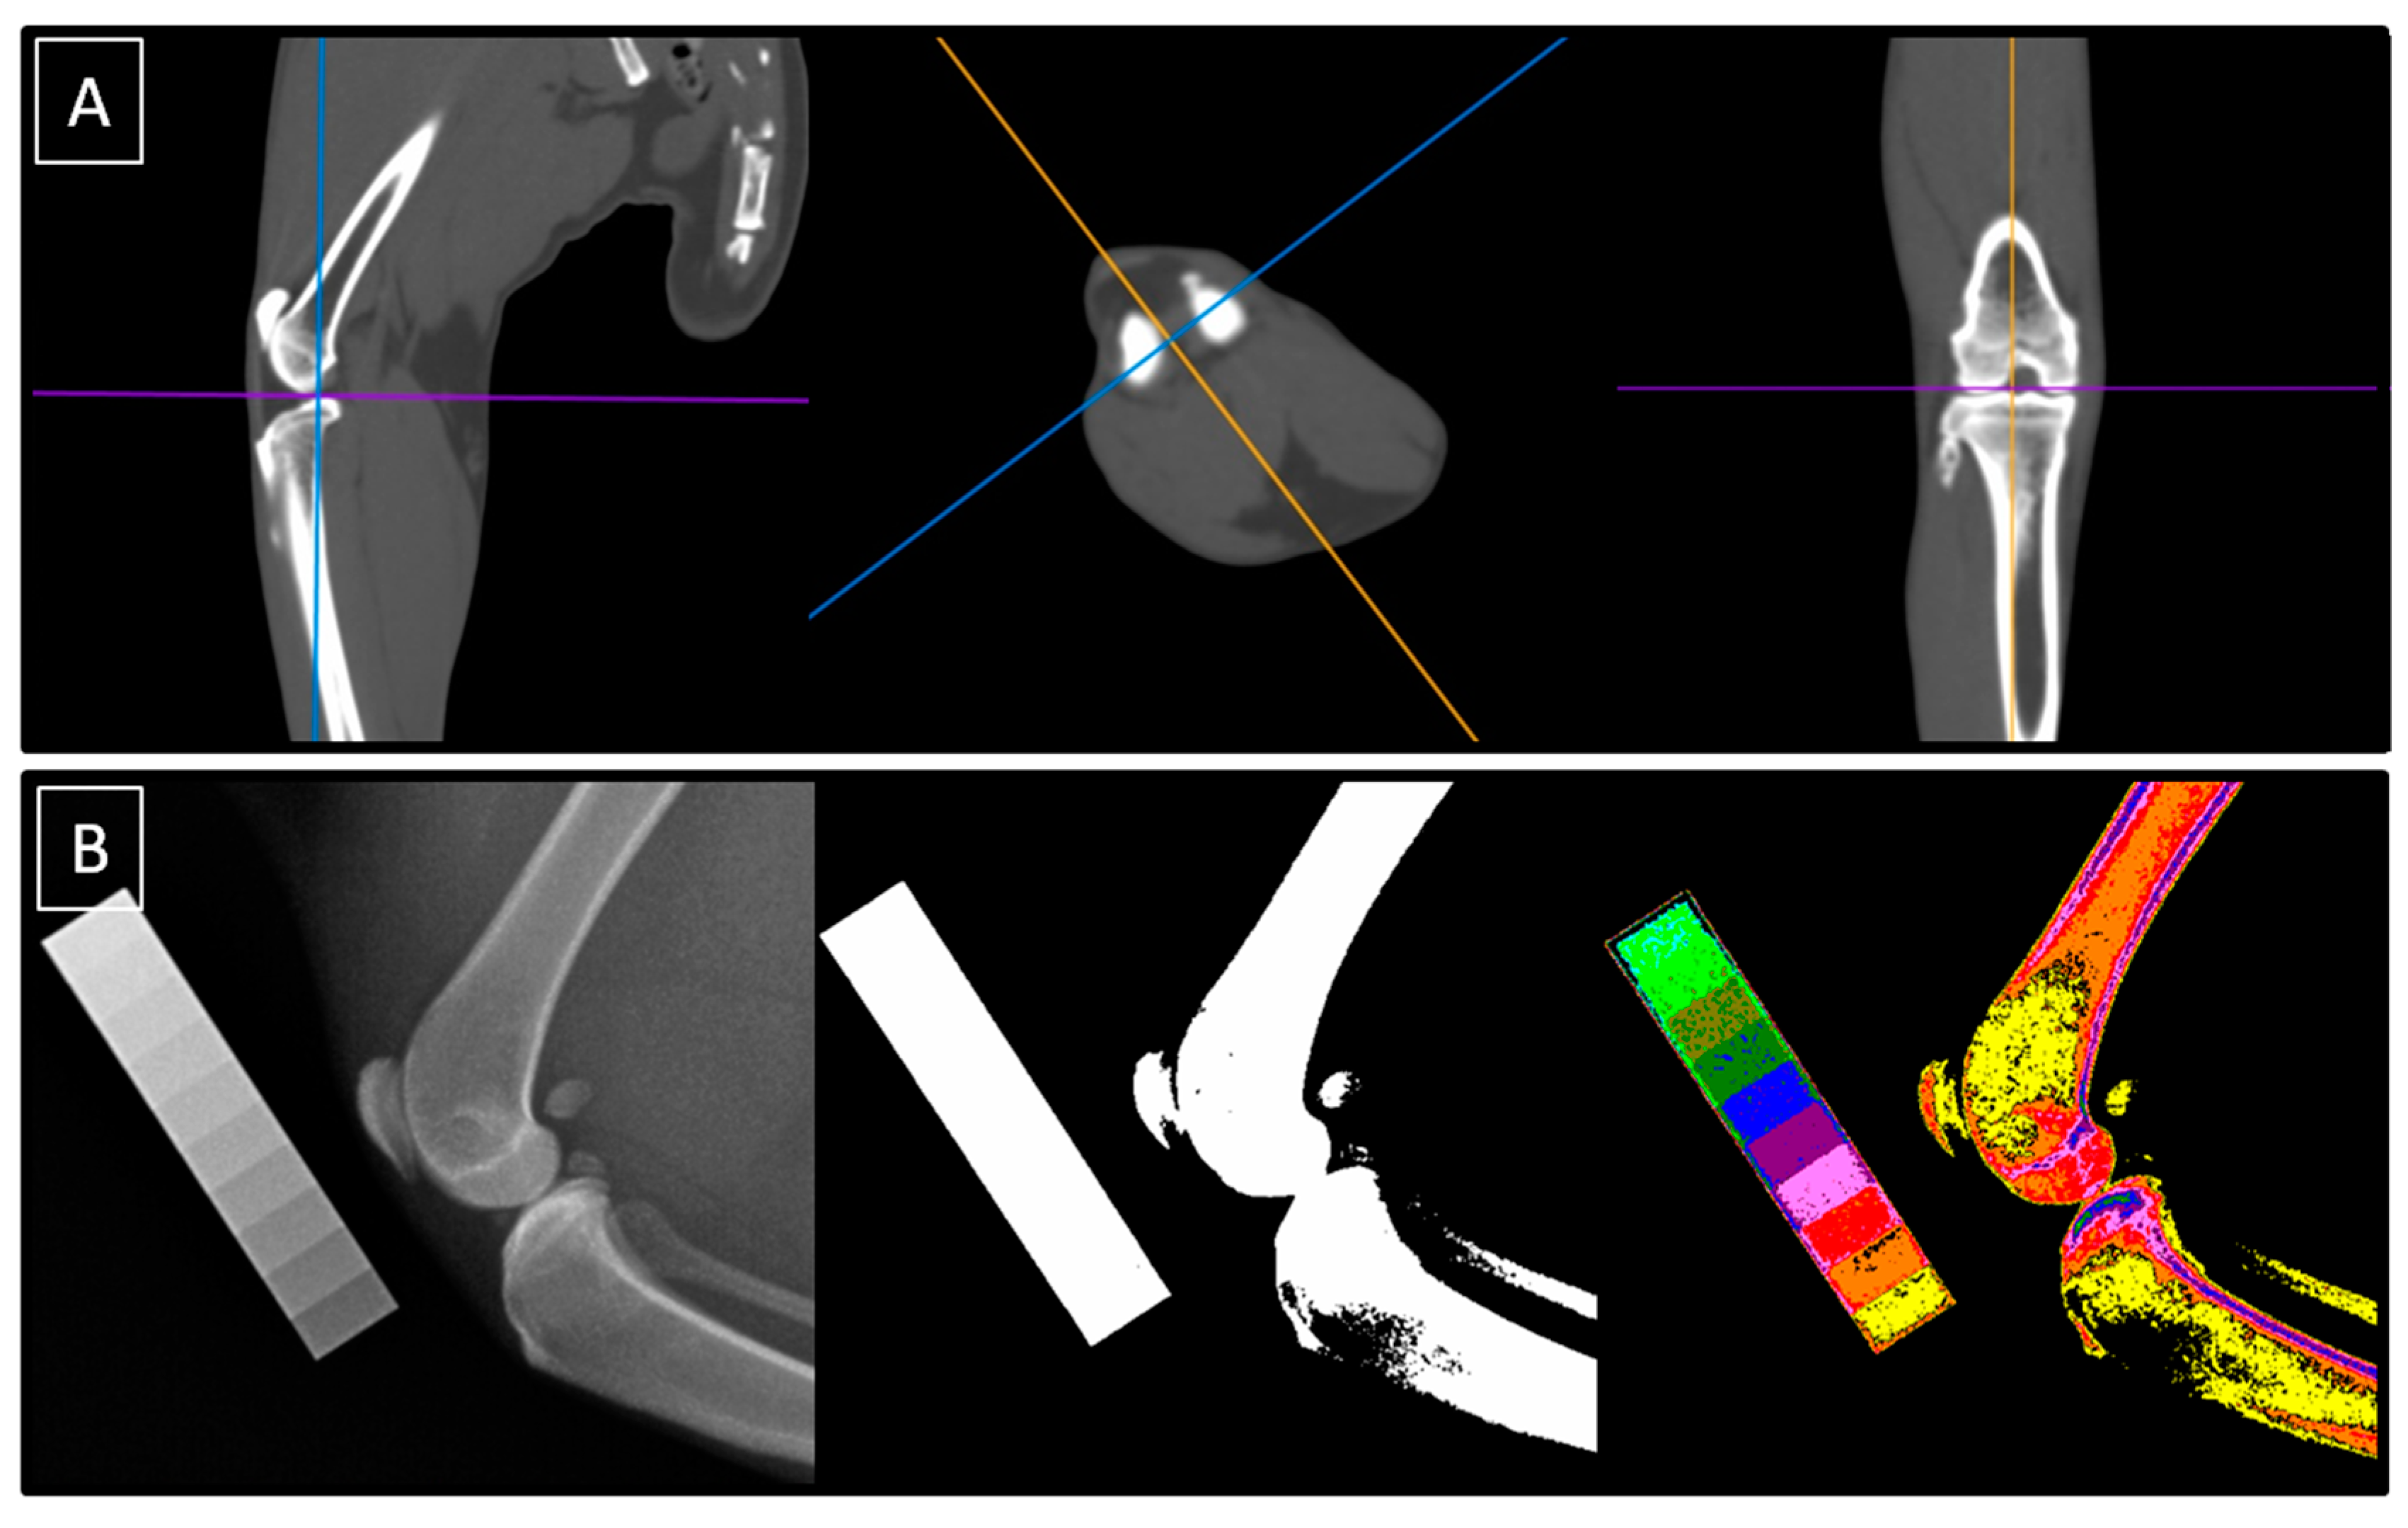

All cats underwent the same protocol for diagnostic imaging of the knee joints. Both the right and left knee joints were imaged in each cat, for a total of 46 knee joints imaged. The imaging protocol included CT and conventional radiography supported by the CDA methods, as shown in Figure 1. Tomograms were qualitatively evaluated in the sagittal, transverse, and coronal planes, while radiographs were decomposed using the CDA method into the white-annotated images representing bone and color-annotated images represented different degrees of X-ray beam attenuation scaled using the aluminum density standard. The CT scans were performed at the Large Animal Clinic, while conventional radiography was performed at the Small Animal Clinic, both at the Institute of Veterinary Medicine at the Warsaw University of Life Sciences.

Figure 1.

The imaging protocol was conducted using both computed tomography (CT) (A) and conventional radiography supported by computed digital absorptiometry (CDA) (B). Tomograms were evaluated in the sagittal, transverse, and coronal planes (A), while radiographs were decomposed using the CDA method into white-annotated and color-annotated images (B).